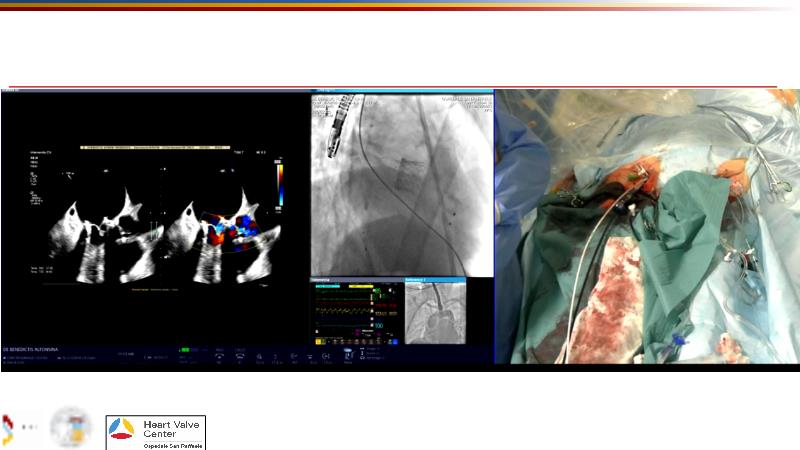

Explore cutting-edge transcatheter valve interventions for mitral and aortic valve disorders, including valve-in-valve procedures and management strategies for paravalvular leakages, and learn about diagnosing and treating mitral annular calcification and transcatheter options in infective endocarditis.

- To get tips and tricks for guidance of transcatheter intervention